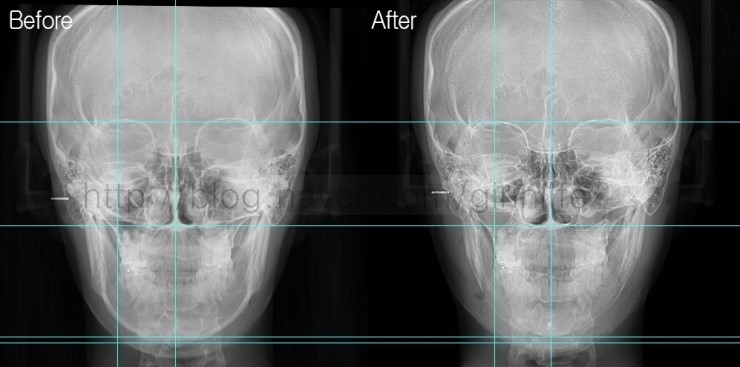

수술전후 차이를 정확하게 말씀드리기 위해 선으로 표시해봤습니다. 턱중앙까지 절골했기 때문에 앞턱 넓이가 좁아졌는데

전문가가 아니면 수술전후 넓이가 얼만큼 차이나는지 구별하기 힘듭니다.

기준선을 보시면 앞턱의 넓이과 길이가 줄어든 것이 확인되시나요?

길이 및 넓이변화를 쉽게 확인하기 위해 기준선을 표시했습니다. 기준선을 놓고 보면변화가 어느정도인지 정확하게 확인됩니다.